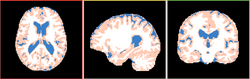

| + | Image:Registration_BRAINSfit.png|NEW: [[Modules:BRAINSFit |BRAINSFit Registration]] (Hans Johnson) | ||

| + | Image:Registration_BRAINSdemonwarp.png|NEW: [[Modules:BRAINSDemonWarp|BRAINSDemonWarp]] (Hans Johnson) | ||

NEW: BRAINSFit Registration (Hans Johnson)

NEW: BRAINSDemonWarp (Hans Johnson)